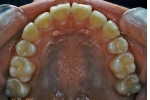

| 初診時